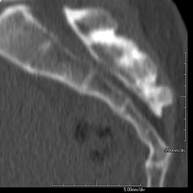

Exploració radiològica que mitjançant un sistema de raigs X i detectors que giren al voltant del pacient i que reconstrueixen les imatges per ordinador, permet l'estudi detallat de l'estern. - TC Clavícules

Exploració radiològica que mitjançant un sistema de raigs X i detectors que giren al voltant del pacient i que reconstrueixen les imatges per ordinador, permet l'estudi detallat de les clavícules. - TC Parrilla costal

Exploració radiològica que mitjançant un sistema de raigs X i detectors que giren al voltant del pacient i que reconstrueixen les imatges per ordinador, permet l'estudi detallat detalla de la Parrilla. - Angio- TC Cardíac o TC Cardíac